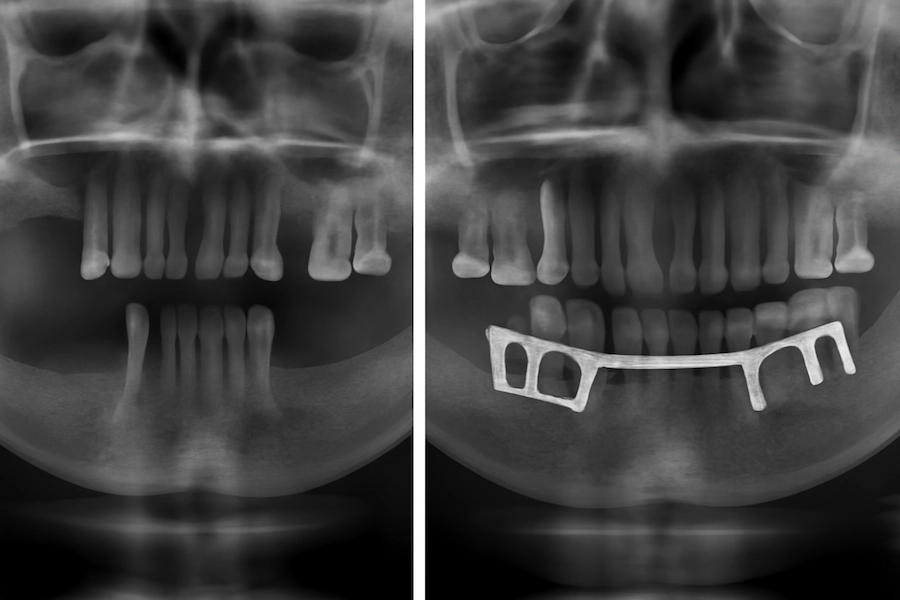

Türkiye’de Subperiostal implantlar öncesi ve sonrası

Subperiostal implant operasyonundan önce, çoğu hastanın ciddi kemik kaybı yaşadığı ve geleneksel implant prosedürlerinin oldukça zor veya imkansız olduğu durumlar mevcuttu. Ancak, hastalar operasyon sonrası fonksiyonlarını geri kazanır, tekrar güvenle gülümseyip yemek yiyebilir duruma gelirler.

İstanbul’da, Türkiye’deki LEMA Kliniği’nde, bu dönüşüm açıkça görülebilir. Kemik kaybı nedeniyle önceden imkansız görülen hastalar, Polen Akkılıç ve ekibinin desteğiyle subperiostal implantlerin muhteşem faydalarını görebilirler. LEMA Klinik öncesi ve sonrası fotoğraflar hem görünüm hem de fonksiyon açısından şaşırtıcı değişiklikleri ortaya koyuyor, hastaların gülümsemeleri ve yiyip içmeleri endişesiz hale geliyor.